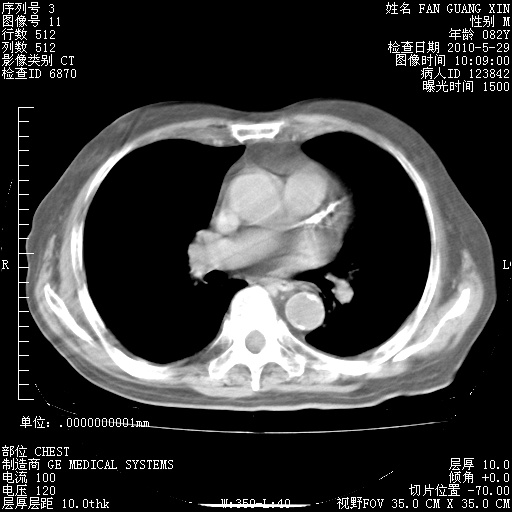

再治疗10天后的肺部CT 纵膈窗

阅读此次胸部CT,肺间质渗出性改变较入院时有吸收。目前从体温、白细胞、中性分叶明显增高,肯定存在细菌感染(发生医院感染哦,若无消化道及泌尿系统等感染的依据,肺部感染可能大)。若你院头孢哌酮舒巴坦钠耐药率较高,同意你的方案,若48小时体温仍高,可考虑使用碳青霉稀类抗菌药物,同时可予超声雾化、注意滴数时加大液体量。白蛋白33.30g/L较低哦,需加强营养等支持治疗。

肺部体征:呼吸25次/分,心率100次/分,呼吸音增粗。无干湿罗音。

血常规:15.36×10 [sup]9[/sup]/L  N0.92  L0.036  M0.045 ESR 27mm/h。

血生化:白蛋白33.30g/L  球蛋白23.67g/L  CRP 32.82mg/L 肝肾功能正常。电解质正常。